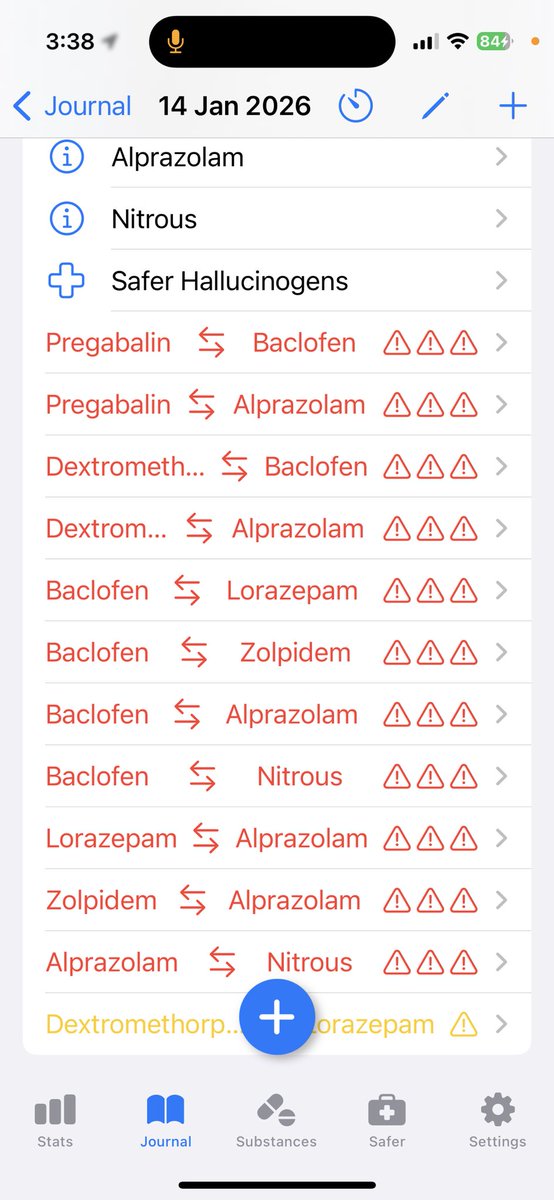

炽烈已极 @AnIncandescence@whitenightX3 journal